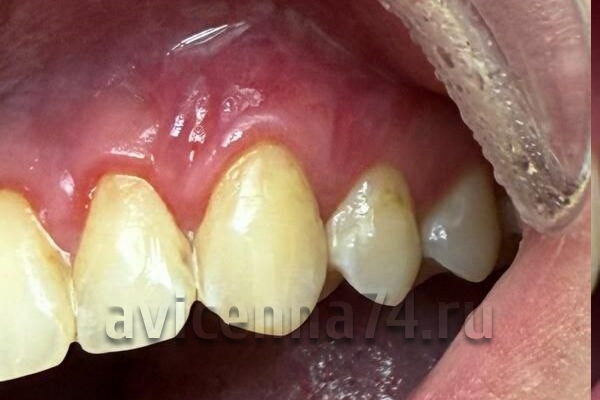

Рецессия десны — это патологическое состояние, характеризующееся апикальным смещением десневого края с оголением шейки и корня зуба. Это не самостоятельное заболевание, а симптом или следствие других патологических процессов в пародонте. Распространенность достигает 10% среди всех заболеваний пародонта, причем у людей старше 50 лет она встречается практически в 90% случаев, а после 80 лет — у 90% пациентов. У детей частота составляет около 8%.

Прогнозы без правильного лечения

Отсутствие терапии приводит к прогрессированию рецессии и тяжелым осложнениям:

1. Гиперчувствительность зубов:

Оголенные корни лишены эмали, что вызывает боль при контакте с холодным/горячим, кислым/сладким.

2. Кариес корня:

Цемент корня менее устойчив к кариесу, чем эмаль. Риск повышается на 40–60% при оголении >3 мм.

3. Эстетические дефекты:

Удлинение зубов, появление «черных треугольников» между зубами, нарушение контура десны.